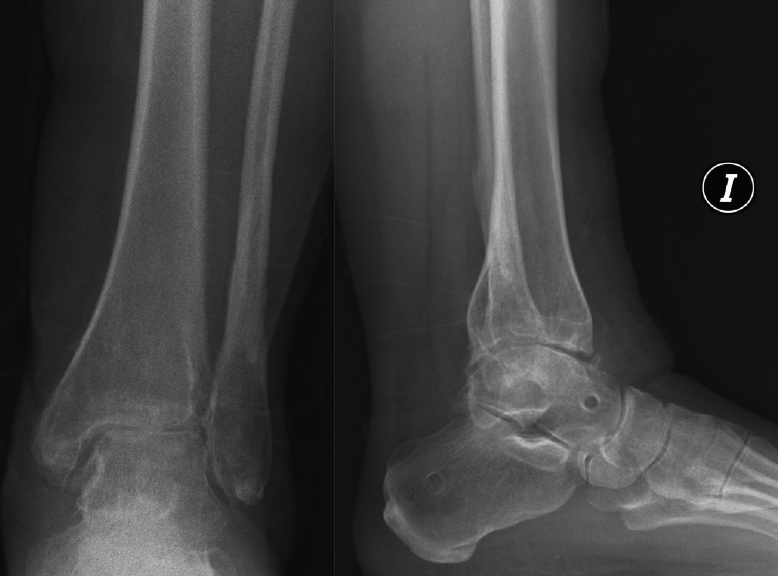

Figura 6. Artrosis postraumática de tobillo tras fractura bimaleolar hace 15 años.

Figura 8. Caso de la Figura 6 a los 3 años de la distracción articulada. Obsérvese el mantenimiento del espacio articular a nivel de la articulación del tobillo.